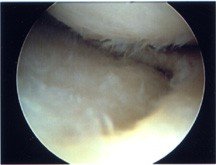

At present the 'gold standard' for diagnosing articular cartilage problems is to take a look directly inside your knee with a small camera in a 'keyhole' procedure called an arthroscopy. Often articular cartilage damage is only identified after an MRI scan or when your surgeon takes a look inside your knee joint with an arthroscope. This can be a real problem due to the length of time it takes to identify that the articular cartilage has been damaged and the implications of this delay.